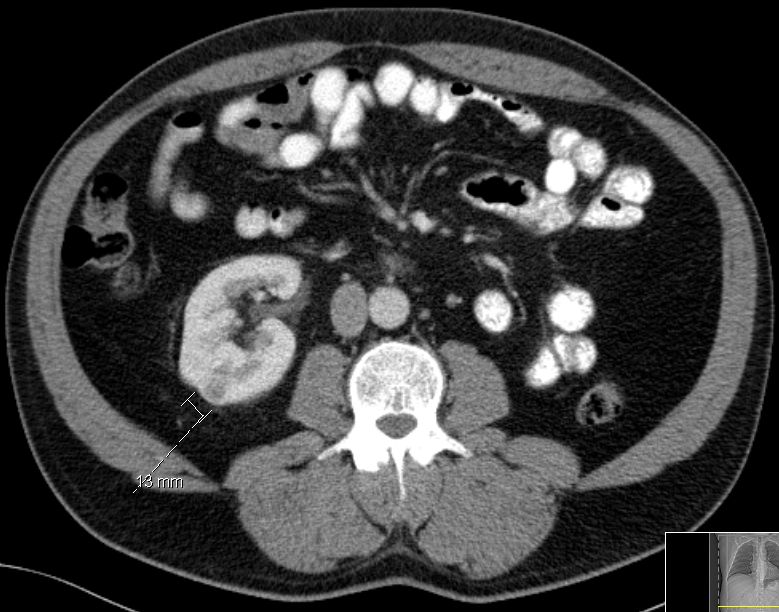

61-jähriger Mann, der vor 7 Jahren

ein Nierenzellkarzinom links hatte. Jetzt ein 13mm großer Herd in der rechten

Niere. Nierenerhaltende Enukleation: Nirenzellkarzinom.![]() | |||